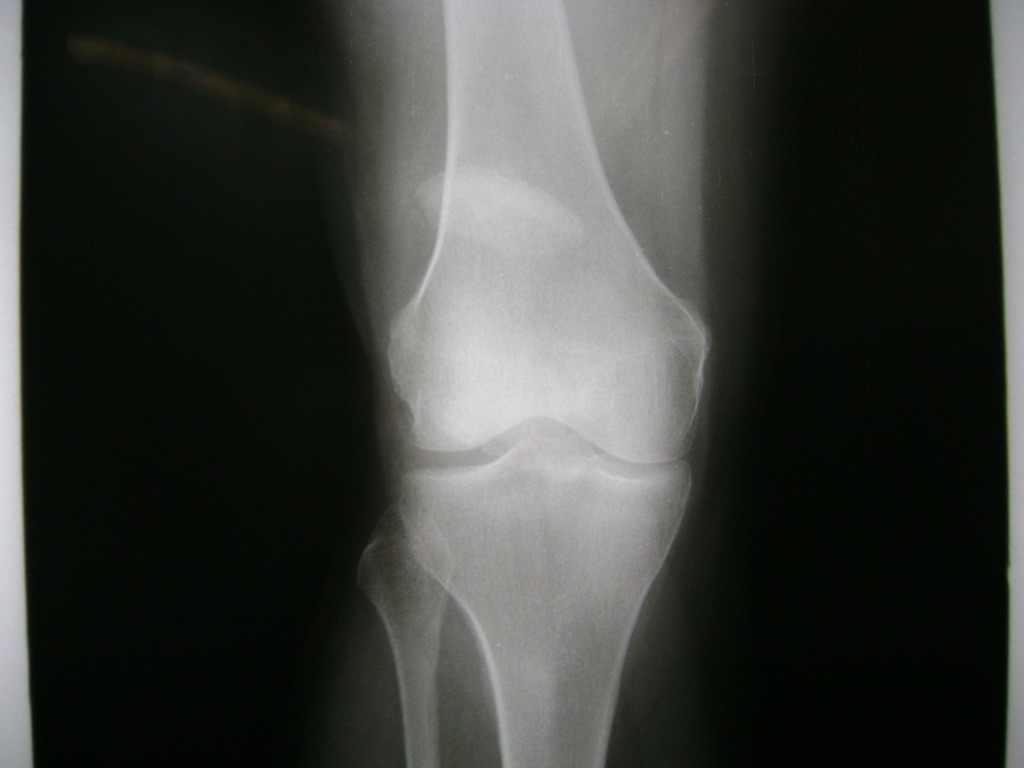

Fémur - Rodilla

La artroscopia de rodilla es un cirugía en el cual la estructura interna de la articulación es examinada ya sea para realizar un diagnostico o para realizar un tratamiento, este procedimiento se realiza utilizando un instrumento parecido a un pequeño tubo llamado artroscopio.